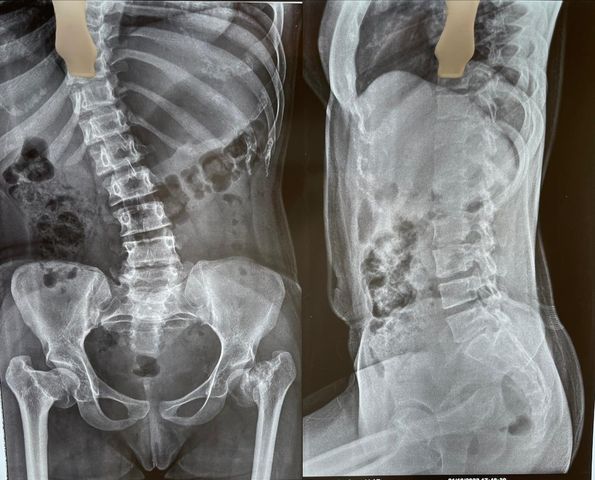

68 year old man ACL (anterior cruciate ligament) reconstruction of Knee

There used to be a common consensus that ACL reconstruction of knee should not be done in old age, this idea has now largely been debunked with statistical evidence. this 68 year old man with a traumatic anterior cruciate ligament tear had intact lateral and medial meniscus and quite normal cartilage in the weight bearing […]